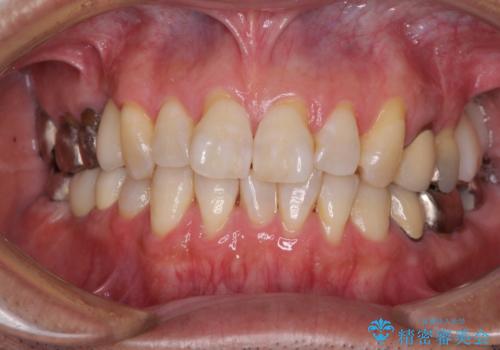

左上の奥歯は2本抜歯が必要であったため、治療期間中は右側に負担がかかり、頻繁に仮歯が壊れてしまいました。

左上に仮歯が装着されたからは咬み合わせが安定し、スムーズに治療を進めることができました。